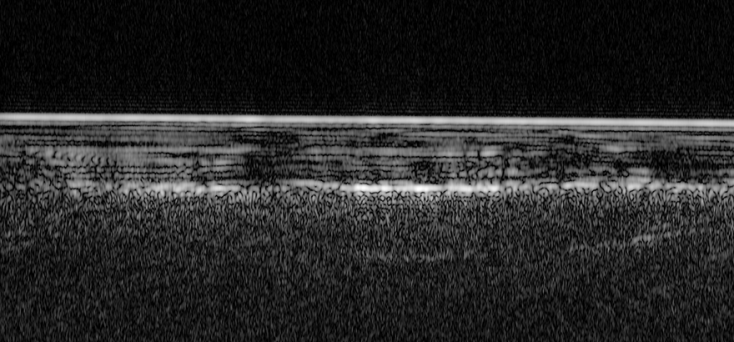

Με άξονα αυτή τη λίμνη, οι Ιταλοί επιστήμονες διεύρυναν τον χώρο των ερευνών τους κατά μερικές εκατοντάδες μίλια χρησιμοποιώντας ακόμα περισσότερα δεδομένα από το διαστημόπλοιο Mars Express της Ευρωπαϊκής Υπηρεσίας Διαστήματος.

Αναλυτικά, στην πρόσφατη μελέτη, η οποία και δημοσιεύτηκε στο περιοδικό Nature Astronomy οι επιστήμονες αναφέρουν ότι η λίμνη που εντόπισαν στο υπέδαφος του Άρη είναι διαμέτρου 20 έως 30 χλμ. και βρίσκεται περίπου 1,5χλμ. κάτω από το παγωμένο έδαφος.

Στην ίδια δημοσίευση προσθέτουν ότι βρήκαν άλλες τρεις μικρότερες λίμνες, ξεχωριστά από την αρχική μεγάλη.